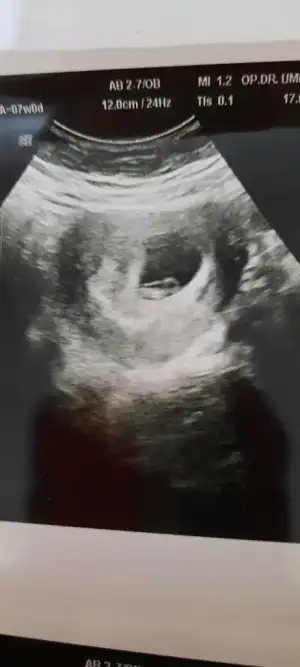

Banada yorum yapabilirmisin?7+4 normal muayene

paşa gibi duruyor7+0 karından ultrason bizimde cinsiyetimizi tahmin edermisiniz?